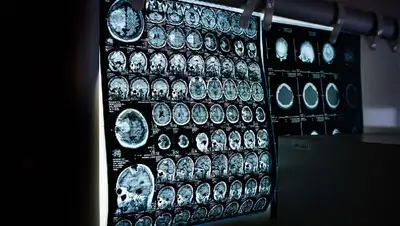

Инсульт – это внезапное и быстрое нарушение кровообращения мозга вследствие закупорки атеросклеротической бляшкой или тромбом (ишемический инсульт) либо разрыва сосудов головного мозга (геморрагический инсульт), из-за чего возникает недостаток кислорода. Последствия инсульта печальны: нервные клетки погибают, приводя к нарушению функций, за которые они отвечали. Чем больше область омертвения в мозге, тем более серьезные последствия имеет инсульт. Виталий Акимов